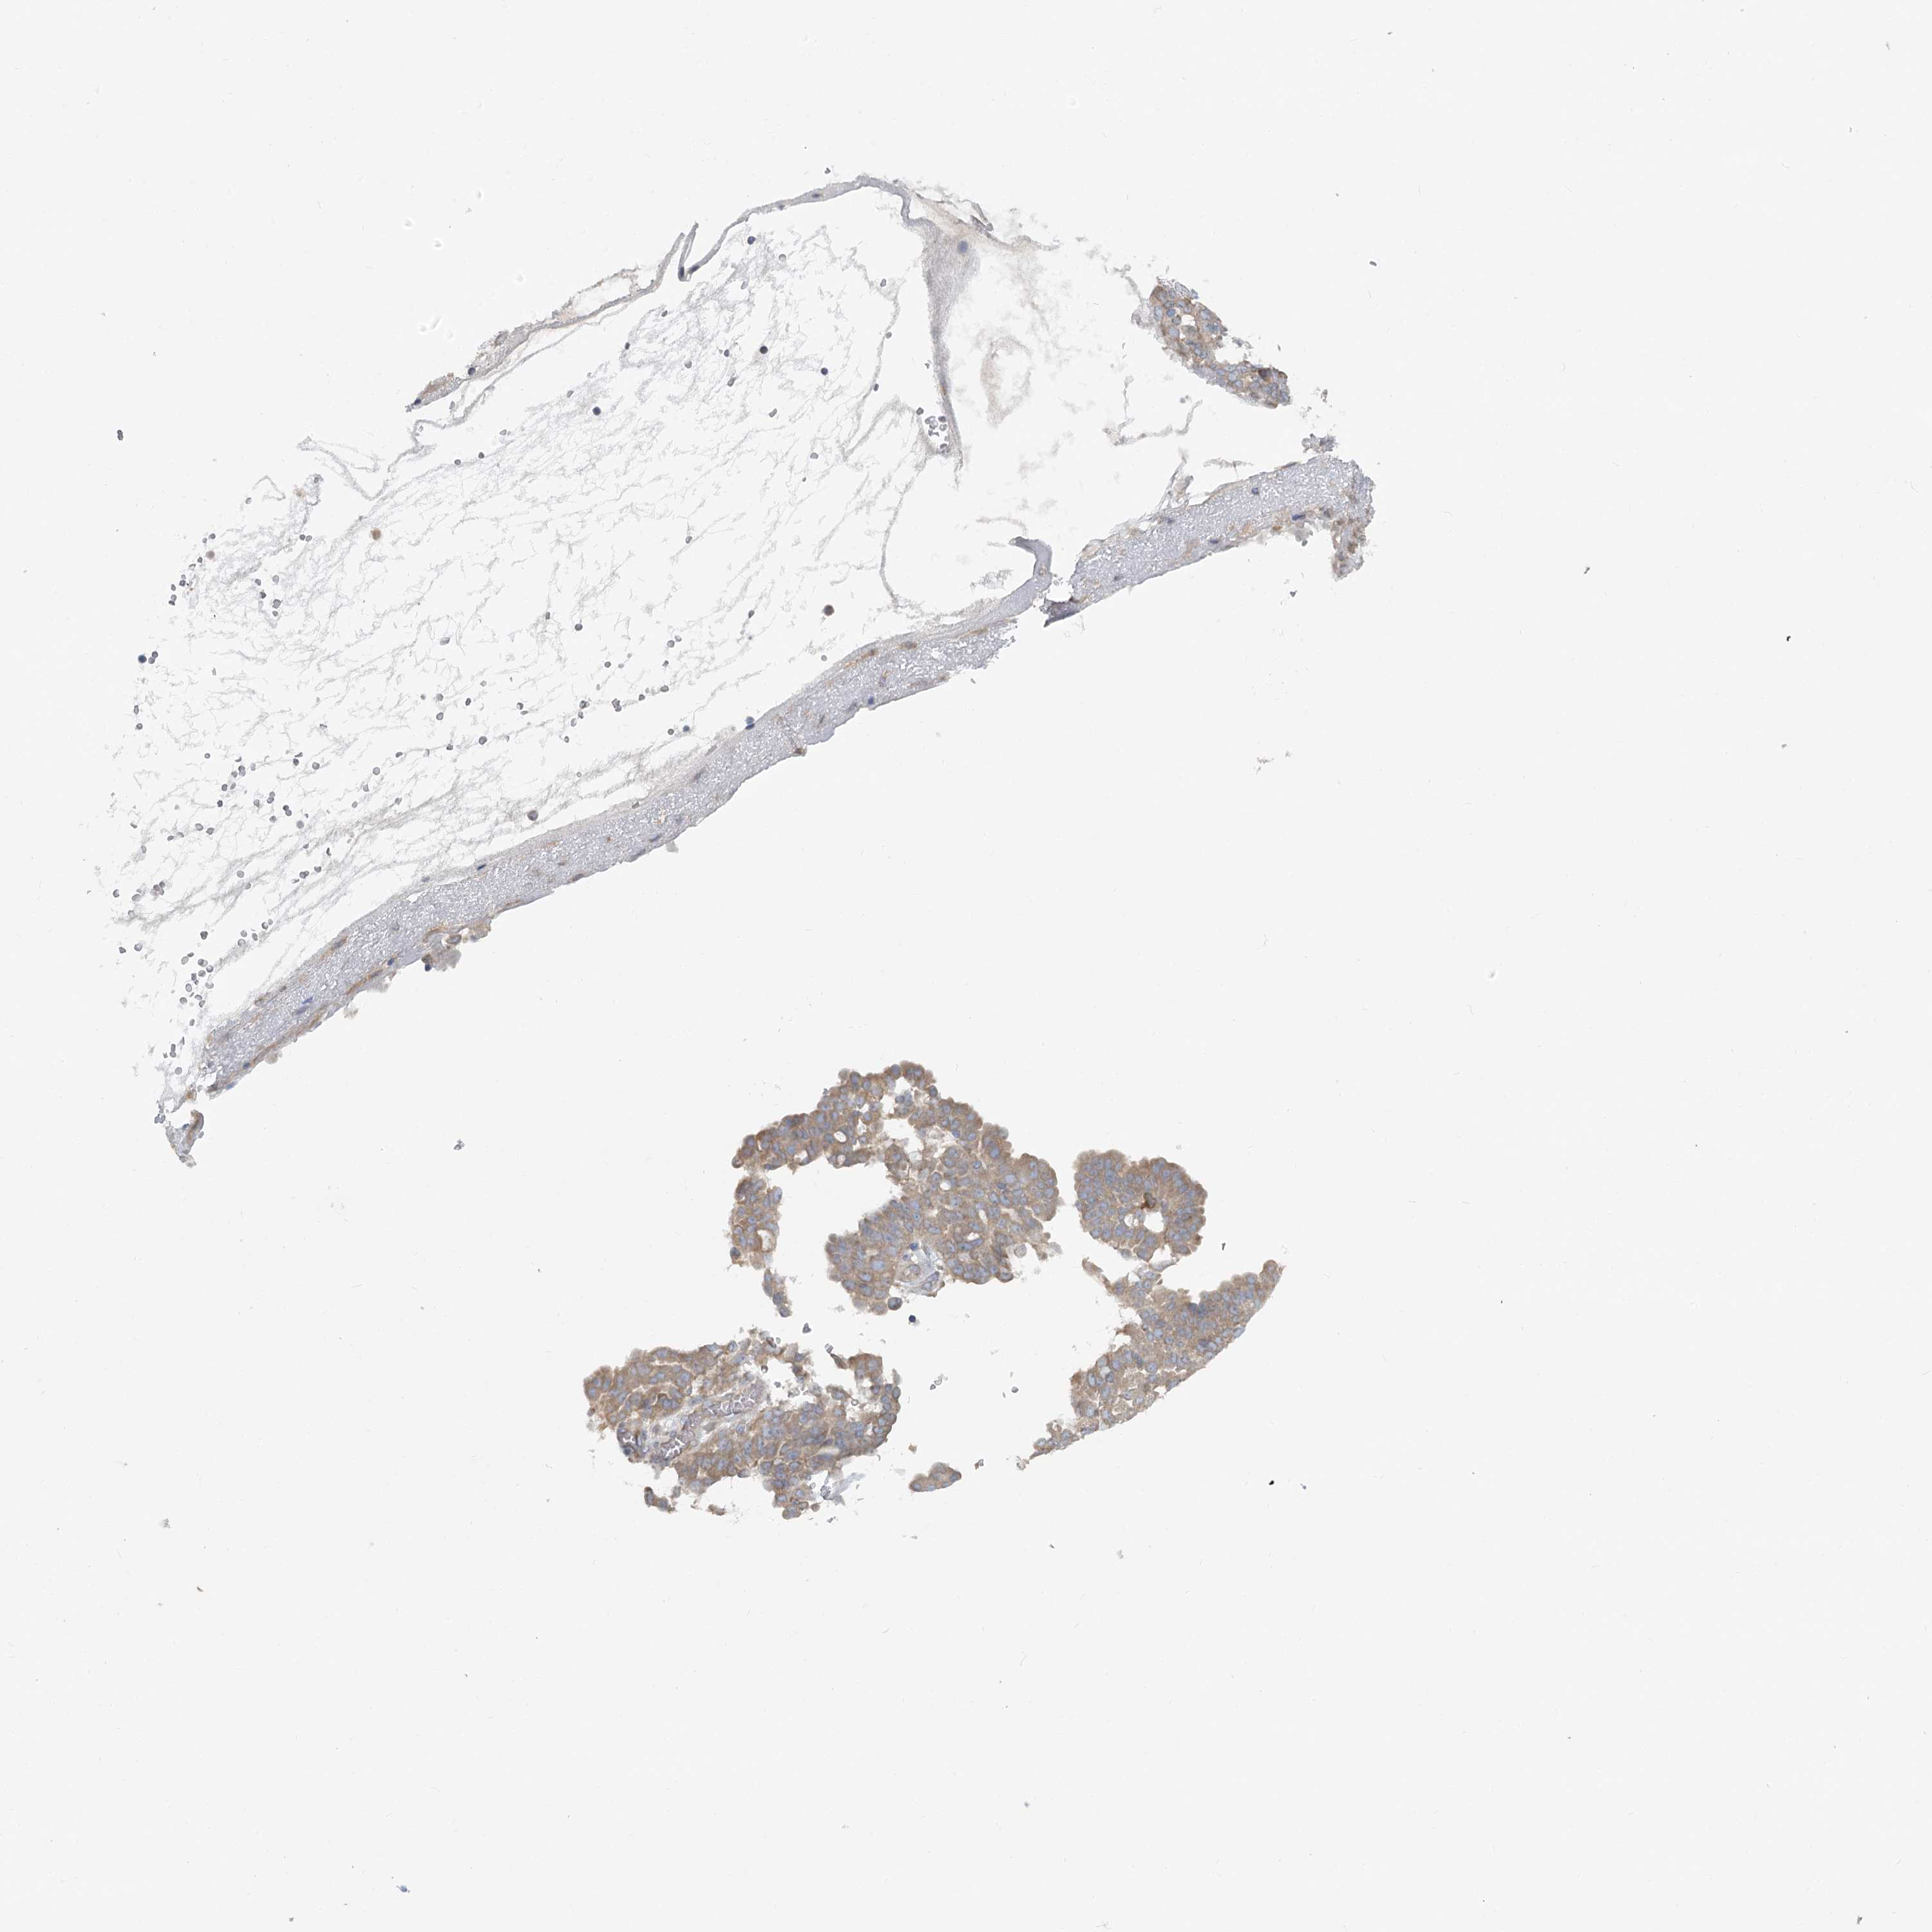

OVARIAN CANCER - Protein expressioni

A mouse-over function shows sample information and annotation data. Click on an image to view it in a full screen mode. Samples can be filtered based on level of antibody staining by selecting one or several of the following categories: high, medium, low and not detected. The assay and annotation is described here.

Note that samples used for immunohistochemistry by the Human Protein Atlas do not correspond to samples in the TCGA dataset.

Antibody stainingi

Antibody staining in the annotated cell types in the current human tissue is reported as not detected, low, medium, or high, based on conventional immunohistochemistry profiling in selected tissues. This score is based on the combination of the staining intensity and fraction of stained cells.

Each image is clickable and will lead to virtual microscopy that enables deeper exploration of all samples and also displays staining intensity scores, fraction scores and subcellular localization as well as patient and tissue information for each sample.

Antibody HPA035945

Antibody HPA056766

Antibody CAB037212

Carcinoma, endometroid

Cystadenocarcinoma, mucinous, NOS

Carcinoma, NOS